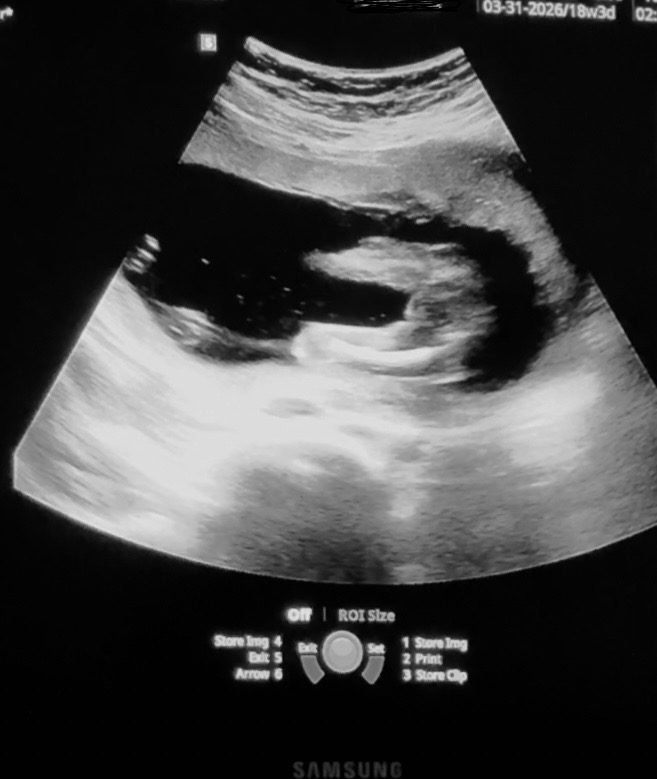

My husband is pushing to wait until the birth to find out gender. I have been on board bc he has wanted this experience of waiting since our first baby and this is our third. We have two girls. However I have been trying to decide to wait with him or find out. I have been inspecting the 18 week ultrasound. The doc tried her best to get this view for the measurement only and avoid revealing any gender. This screen shot is the closest it got to showing anything. What do y’all think? Boy or girl?

• I'll be frank, I think girl. I think I can faintly see labia? But with my oldest we were told at two ultrasounds (16 and 20 wks) that he was a girl and you'll notice that that doesn't math lol. I would suggest you try and stick it out and not find out without him though if you're on board, I know for me personally I wouldn't trust myself to not slip up in some way in the next 4-5 months and it would be a bummer if it got ruined right before the birth.

• I also think it’s a girl. My boys, and I have a lot, never have those 3 lines. I would stick it out too because it will be a fun experience for both of you.